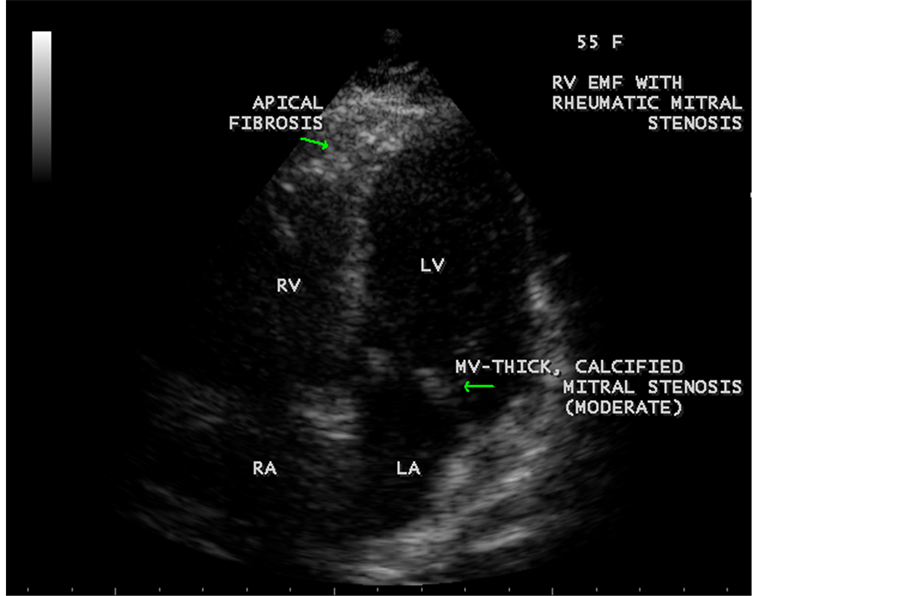

Figure 63. RV EMF associated with rheumatic mitral stenosis in a 55-year-old female.

ventricle”) in a 16-year-old female as shown in Figure 50 to Figure 53 were detected. RV EMF with rheumatic involvement of mitral valve as shown in Figure 54 and Figure 55 in a 44-year-old female and in Figure 63 in a 55-year old female. Biatrial enlargement due to rheumatic atrioventricular (AV) valves (mitral and tricuspid) involvement characterized by stenosis of the valves are illustrated in Figure 56 to Figure 59 in a 54-year-old female and it is differentiated from EMF which is characterized by AV valve regurgitation as shown in Figure 34 and Figure 60. RV EMF associated with thickening and fibrosis of moderator band in a 16-year-old female was shown in Figure 46. RV EMF associated with apical left ventricular hypertrophic cardiomyopathy was shown in a 47-year-old male as in Figure 61 and in a 65-year-old female as in Figure 62.